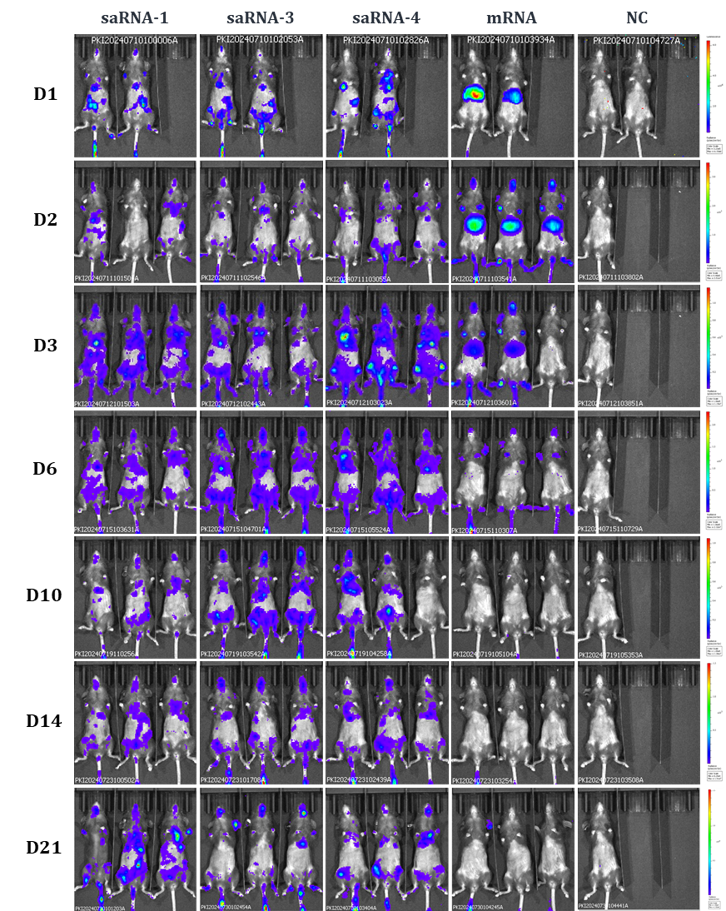

100ng of GS-saRNA-1 or GS-saRNA-2 vector based eGFP saRNA (5-methylcytidine) were transferred into HEK293T cells using LNP or Lipofectamine MessengerMAX (Thermo Fisher). 24 and 48h after transfection, eGFP expression is observed by fluorescence microscopy.